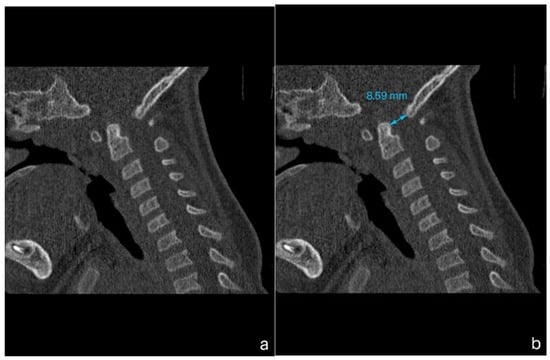

A 1-year-old boy with achondroplasia, measuring 71 cm in height and 8400 g in weight, experienced a whiplash injury. The mechanism of injury was described as follows: “After the mother threw the child up in the air and caught him, his head jerked violently, following which he became motionless”. The patient was regularly monitored for achondroplasia at another medical center without any mention of foramen magnum stenosis. Upon admission, the patient presented with signs of achondroplasia, including macrocephaly, a depressed nasal bridge, and a large fontanel measuring 2 × 2 cm. At birth, the patient’s head circumference was 39 cm, and it was 51 cm at the time of admission. A neurological examination revealed acute flaccid tetraparesis with a Medical Research Council (MRC) grade 1/5 in the upper extremities and MRC grades 2–3 in the lower extremities. No other neurological deficits were observed. Initial craniocervical computed tomography demonstrated a reduced volume of the posterior fossa, foramen magnum stenosis, and ventriculomegaly, without any fractures or dislocations (Figure 1a,b). However, magnetic resonance imaging (MRI) revealed foramen magnum stenosis and pathological signal changes in the medulla oblongata, cervical spinal cord in segments C1 and C2, and the posterior atlantoaxial ligament. Additionally, morphological changes in the skull base and basilar impressions were observed (Figure 2a). The patient was monitored in the PICU and experienced an episode of hypoxemia, with an oxygen saturation of 79% on the first night after the injury. This episode resolved spontaneously after administering oxygen through a face mask for 10 min at a rate of 3 L/min. The patient remained respiratory and hemodynamically stable and did not experience any complications. He was breastfed and exhibited no swallowing disorders. Symptomatic treatment included regular analgesia with metamizole, supplemented by rectally administered paracetamol and the use of a soft cervical collar. The neurosurgeon recommended delaying the surgical therapy based on established principles to minimize the risk of intraoperative lesioning of compressed neural structures during the acute phase of the injury and to allow sufficient time for the edema-related compression of neural tissues to subside. A gradual remission of neurological symptoms was observed, and a microsurgical decompression was finally performed two weeks after the injury, after the flaccid tetraparesis subsided gradually to a MRC grade of 3/5 for the upper extremities and to an MRC grade of 4/5 for the lower extremities.

Figure 1.

Computed tomography (CT) imaging of a child with achondroplasia following a whiplash injury. (a) Sagittal plane bone window CT scan demonstrating stenosis at the craniocervical junction, with no fractures or dislocations present. (b) Sagittal plane bone window CT scan highlighting a reduced dens-opisthion distance, with the anteroposterior diameter at the C2–C0 level measuring 8.5 mm.